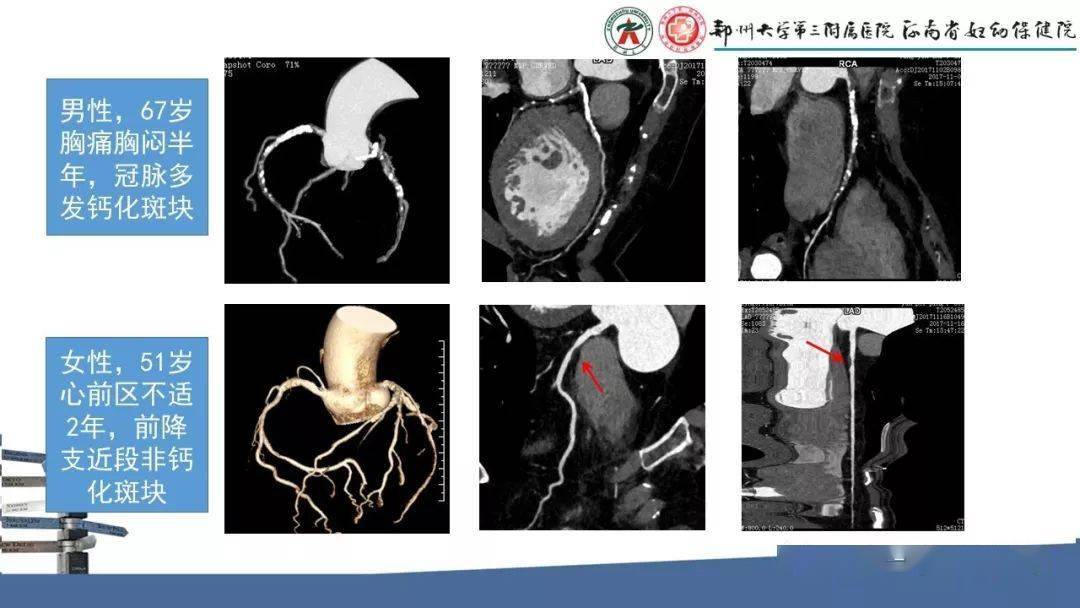

ct在评估冠脉斑块性质方面有独特优势,可以"精准"识别"易损斑块",为"

如何分析冠状动脉cta